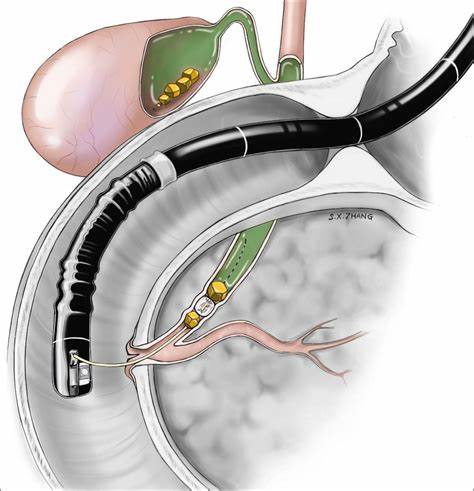

6-4. 담석에 의한 췌장염

1) 내시경적 역행성 담췌관조영술(ERCP)

- 담석 혹은 담도염의 증거가 있는 경우에 시행한다. 뚜렷한 증거 없이 진단적 목적으로 시행하지 않는다.

2) EUS(endoscopic ultrasound, 내시경초음파)와 MRCP(MR cholangiopancreatography, 자기공명담췌관조영술)

- 임상적으로 담관염의 증거는 없지만 담석에 의한 췌장염이 의심되는 경우 EUS 혹은 MRCP를 시행할 수 있다.

- EUS는 미세담석을 찾는데 좀 더 효과적이며, MRCP는 상대적으로 덜 침습적인 장점이 있다.

6-5. 중재적 치료

- 증상이 수 주 이상 지속될 때

- 내과적 치료에도 장기부전이 1주 이상 지속될 때

- 감염이 동반되어 있으며 내과적 치료만으로 호전되지 않을 때

- 압박에 의한 장폐색, 담도폐색이 있거나, 췌도가 손상되었을 때

-> 일차적으로는 경피배액술(PCD, percutaneous drainage) 혹은 내시경을 이용한 내배액술(internal drain)을 시행해 볼 수 있으며, 이러한 치료에도 효과가 없는 경우엔 수술적으로 괴사조직 제거를 시도할 수 있다. 수술은 보통 췌장염 발생 4주 이후에 시행하는 것이 권고된다.